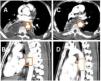

Unfortunately, 17 days after surgery, on Eid day (a national holiday), the patient arrived at the emergency room, having presented with 6–8 episodes of hematemesis. The patient was resuscitated with blood products, tranexamic acid, and vitamin K. His hemoglobin dropped from 7.7 to 5.6 over the next 20 h. A CT scan found an aneurysm at the T6 level on the anterior aspect of the aorta, measuring 10 × 7 mm, with a fistulous connection to the anastomotic site (Fig. 1A–C). There was no pleural leakage and no communication with the thoracic cavity. Endoscopy revealed a large adherent clot and fresh blood at the anastomosis site. Endoscopic attempts to close the fistula with endoclips (Fig. 1D) were unsuccessful. Urgent aortic stenting was performed, and follow-up CT angiography showed that the stent (length 2.9 cm) partially covered the fistulous communication (Fig. 2A and B). Re-stenting with a 4.6 cm stent completely covered the fistula (Fig. 2C and D). The patient was extubated and a nasojejunal tube was inserted. He was discharged on day 10, with long-term oral antibiotics. The patient’s post-operative rehabilitative state is good, and he is undergoing regular surveillance.

(A) Axial and (B) sagittal views of the initial CT scan, showing fistulous communications between the aorta and gastric conduit. (C) Endoscopic image showing a hematoma (red arrow) and some active bleeding from the fistula site. (D) Endoscopic image showing the attempted endoscopic clipping (white clips).